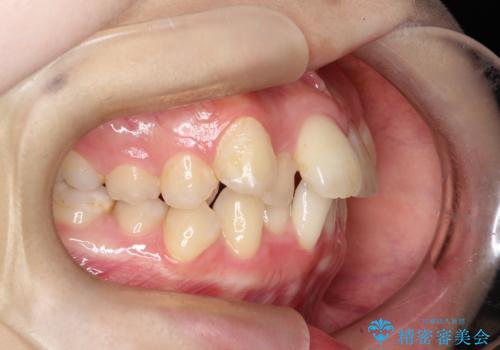

- 「歯のデコボコ、八重歯、口ボコが気になる」を主訴に来院された患者様です。

上下左右4番(4本)の歯を抜歯しワイヤー矯正で治療を行いました。

計4本の抜歯を行い、歯のデコボコと口元がすっきりし、大変ご満足していただけました。